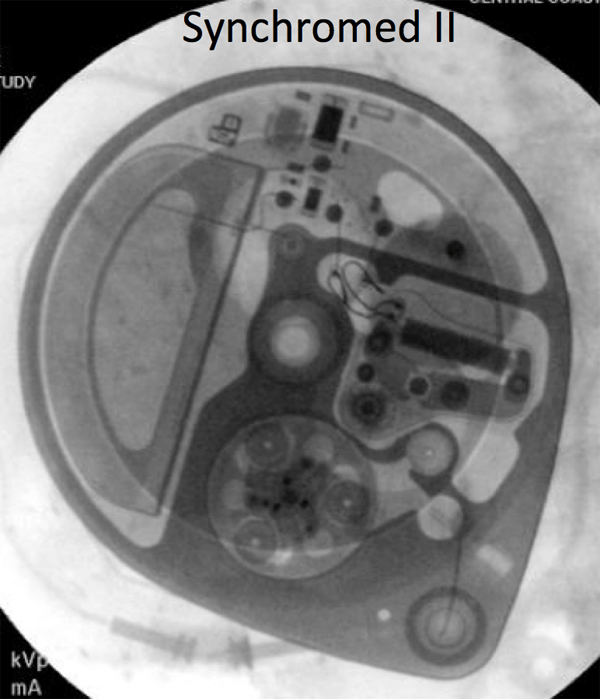

- A policy is being developed with the Pain Management Service to expedite the scanning of patients with Medtronic Synchromed II pumps, which are MRI conditional at 1.5T. The identity of the pump must be documented before the MRI scan, and then confirmed at the time of the scan.The pump program needs to be check after the MRI: for outpatients, this can be done at a pre-scheduled appointment with the managing service; inpatients will need to have the Pain Management team perform this check.

If there is any doubt about the suitability of a device for MRI, or about management of a device before and after MRI, contact the Neuromodulation Service ([email protected]). Below are x-ray images of the common Synchromed II pump and the two pumps that should not be imaged without outside consultation and management: Prometra I and II pumps.